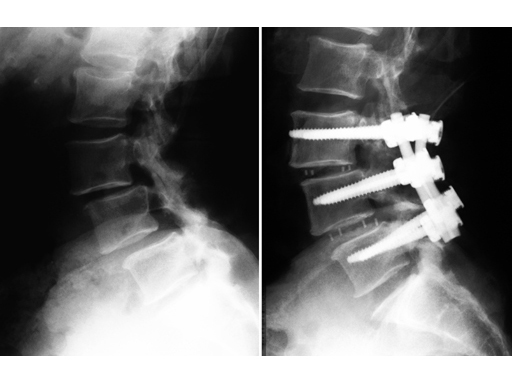

64-year-old woman, lateral, pre- and postoperative x-rays.

For the surgical treatment of degenerated lumbar discs, cages can be used in order to restore disc height and the lordotic curve. A mechanically stable and durable device such as PLIVIOS or Contact Fusion Cage can be used. The new PLIVIOS implants are based on the clinically established PLIVIOS and Vertebral Spacer-PR concept. The open structure and the interface to the implant holder is the same. In order to ease the rotation of the implant, one row of teeth has been removed and is replaced by a chamfer. The cross-section is adapted to the Contact Fusion Cage sizes of 7 8 mm, 9 8 mm, 10 8 mm, 11 9 mm, 12 10 mm, 13 10 mm, and 15 11 mm. The implants provide two lordotic angles of 4 and 8. All implants are available empty or prefilled with chronOS block material. PLIVIOS provides benefits in dorsal arthrodesis with cage by preserving the integrity of the endplates and their stability.